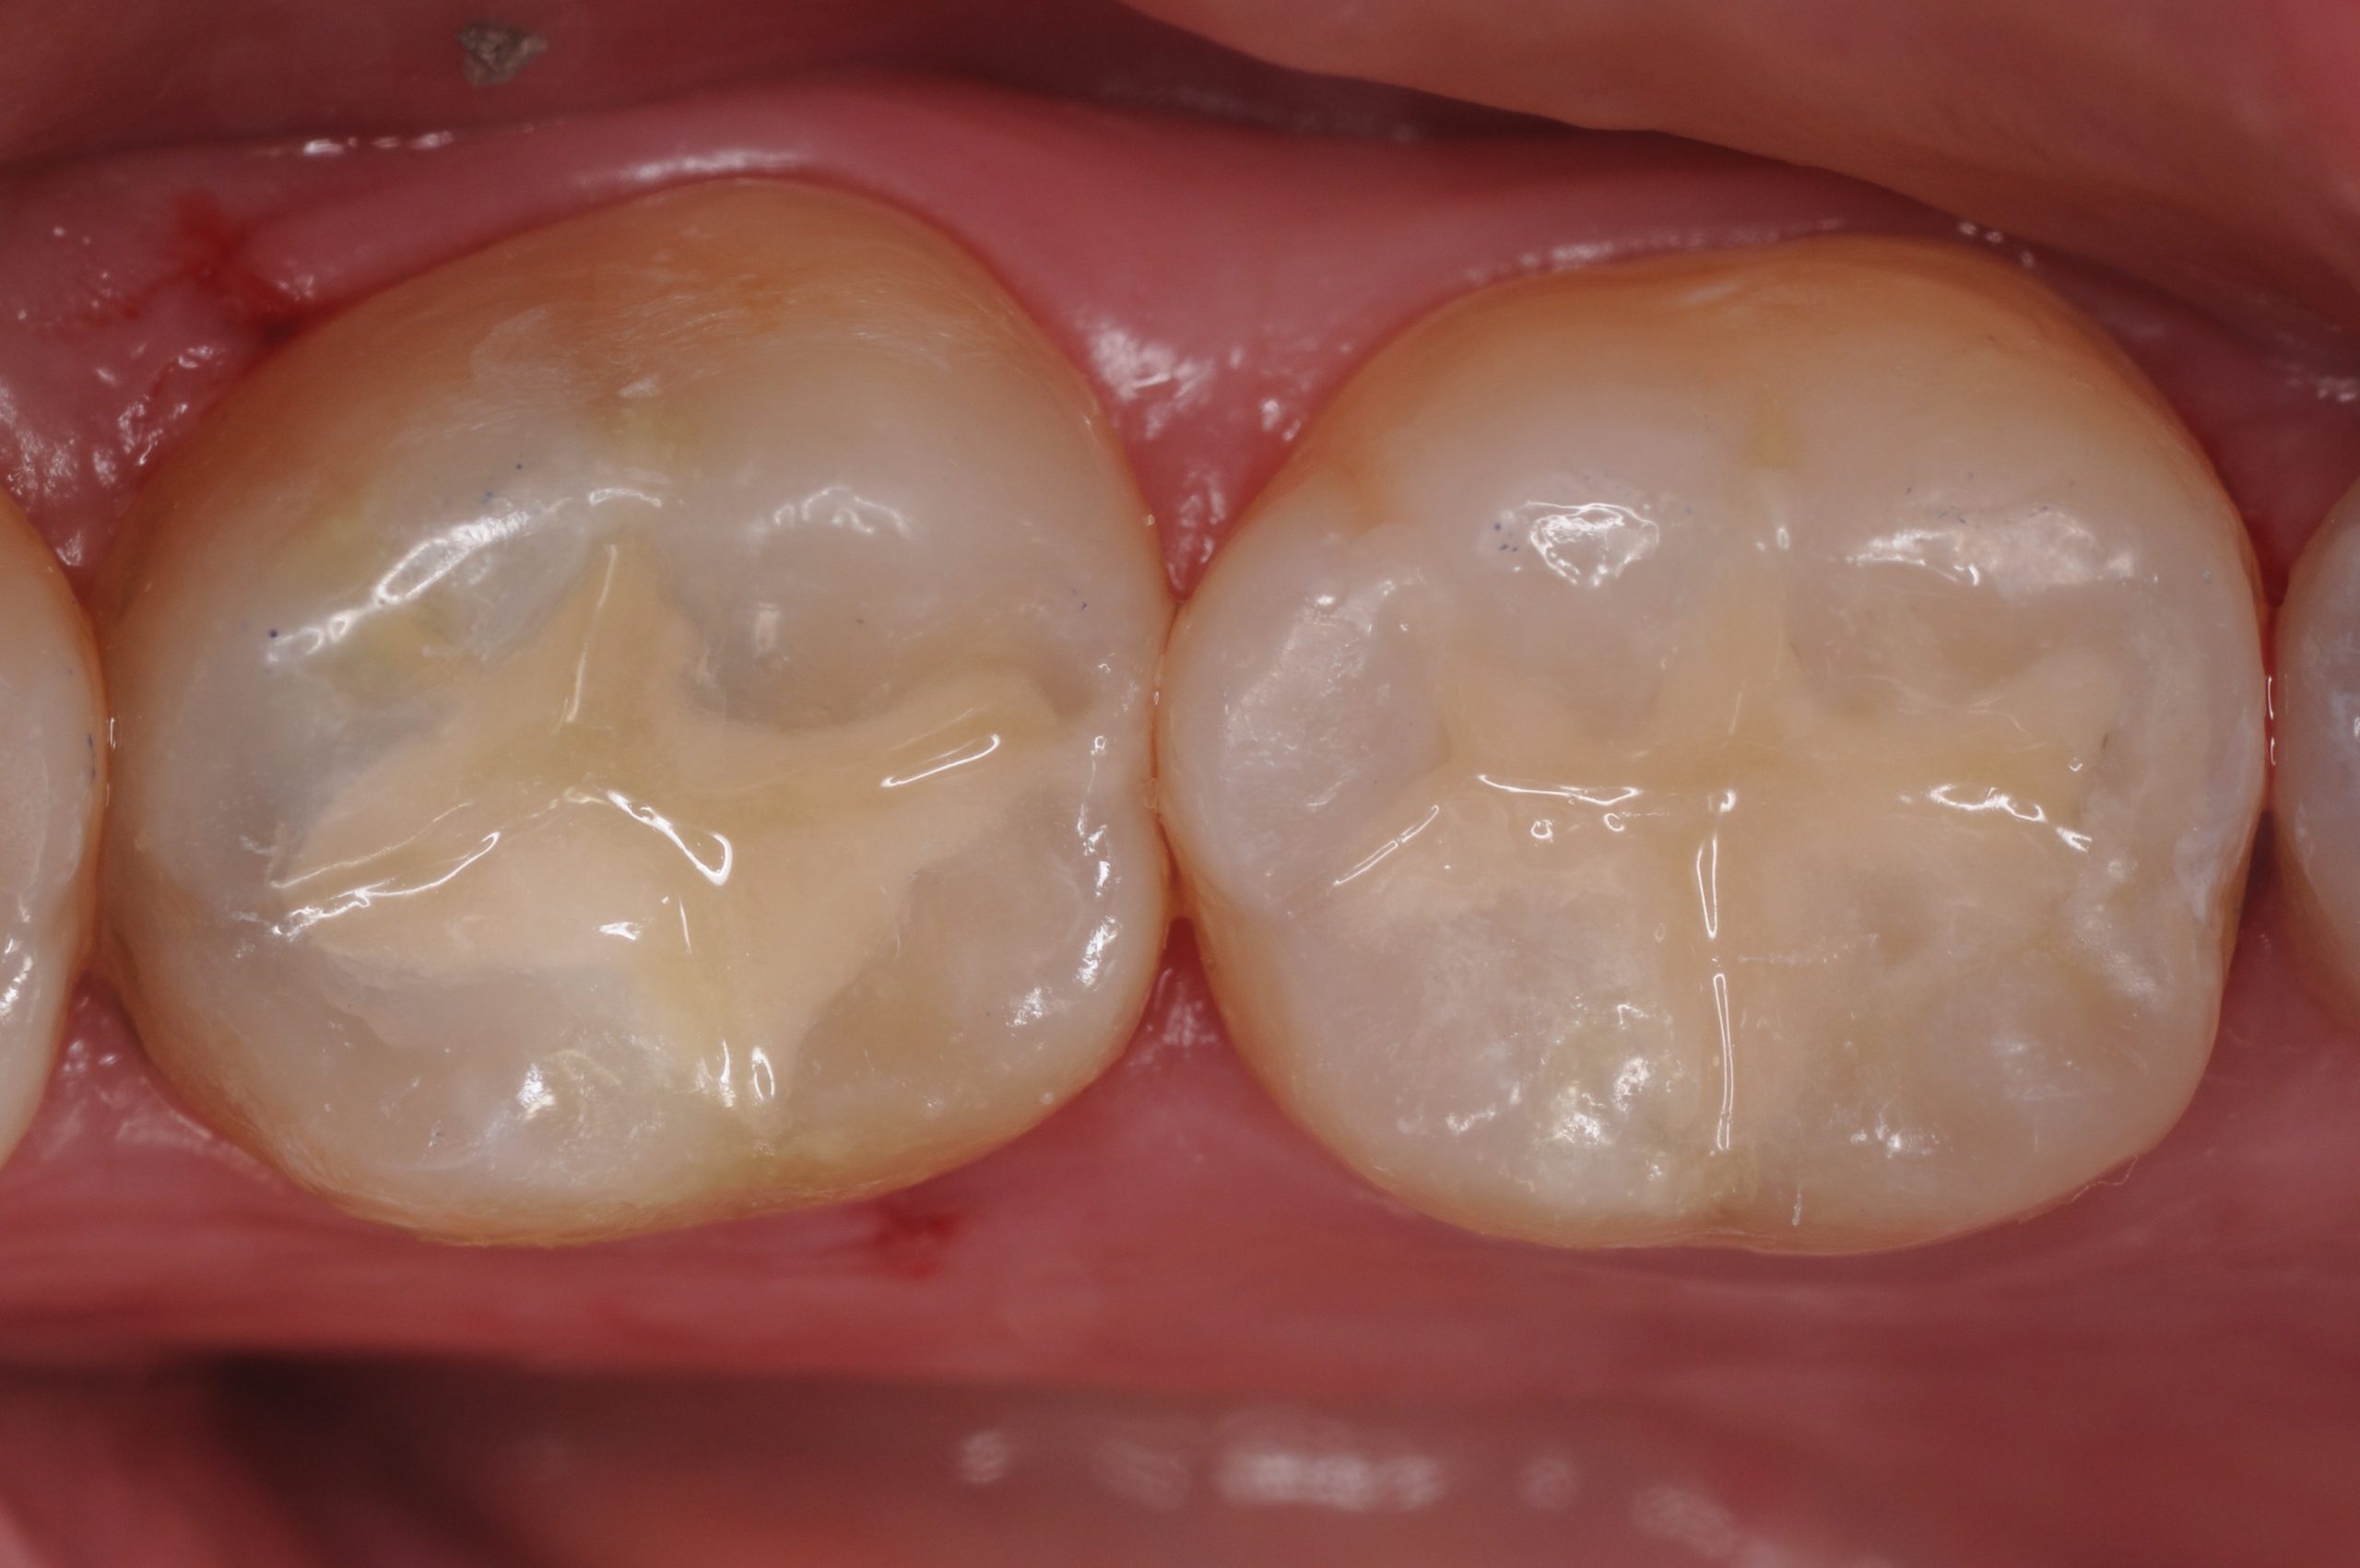

Completed esthetic restorations on teeth #18 and #19 with smooth finish, natural appearance, and functional integrity.